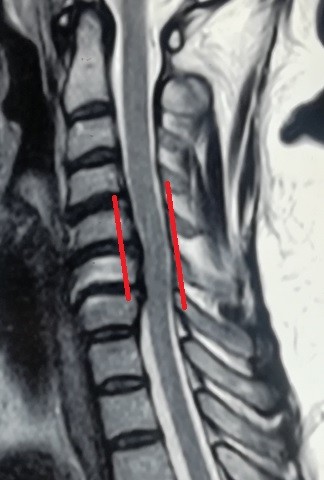

multiple cervical herniated discs